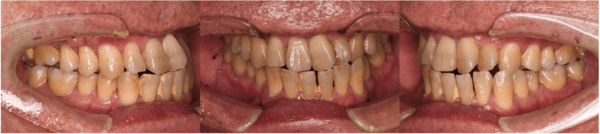

| 年齢 | 56歳・男性 |

|---|---|

| 主訴 | 定期検診 |

| 治療内容 | 歯周基本検査・歯石除去・着色除去・フッ素塗布 |

| 治療期間 | 60分 |

| 費用 | 保険診療約4,500円 (歯の本数や検査内容で料金が変動します。) (2023/12/25時点の価格) |

| リスク・副作用 | ・歯ぐきの炎症がある場合は歯石除去中に出血を伴う可能性があります。 ・処置後に歯がしみることがあります。 ・歯ぐきの炎症が軽減すると歯ぐきが引き締まり、歯が長く見えることがあります。 ・定期検診は予防の一環であり、検診の来院で必ず虫歯や歯周病にならない訳ではありません。 |

| 担当者所見 | ブラッシング指導後、歯石除去を行い定期検診へ移行 矯正治療を行う予定 |

| 特記事項 | 交叉咬合・かみ合わせが強い |

| 担当者所見 | 初診時は歯石が全顎的に付着しており、歯石除去時は出血もありました。特に下の前歯は歯と歯の間を埋めるように多量の歯石が付着していました。ブラッシング指導も行い、定期検診へと移行しました。 定期検診時は全体的な清掃状態も良好で、ご自身も歯ブラシを頑張っているとおっしゃっていました。矯正治療開始後も綺麗で健康な口腔内を維持する為、定期検診を継続的に行っていく予定です。 |